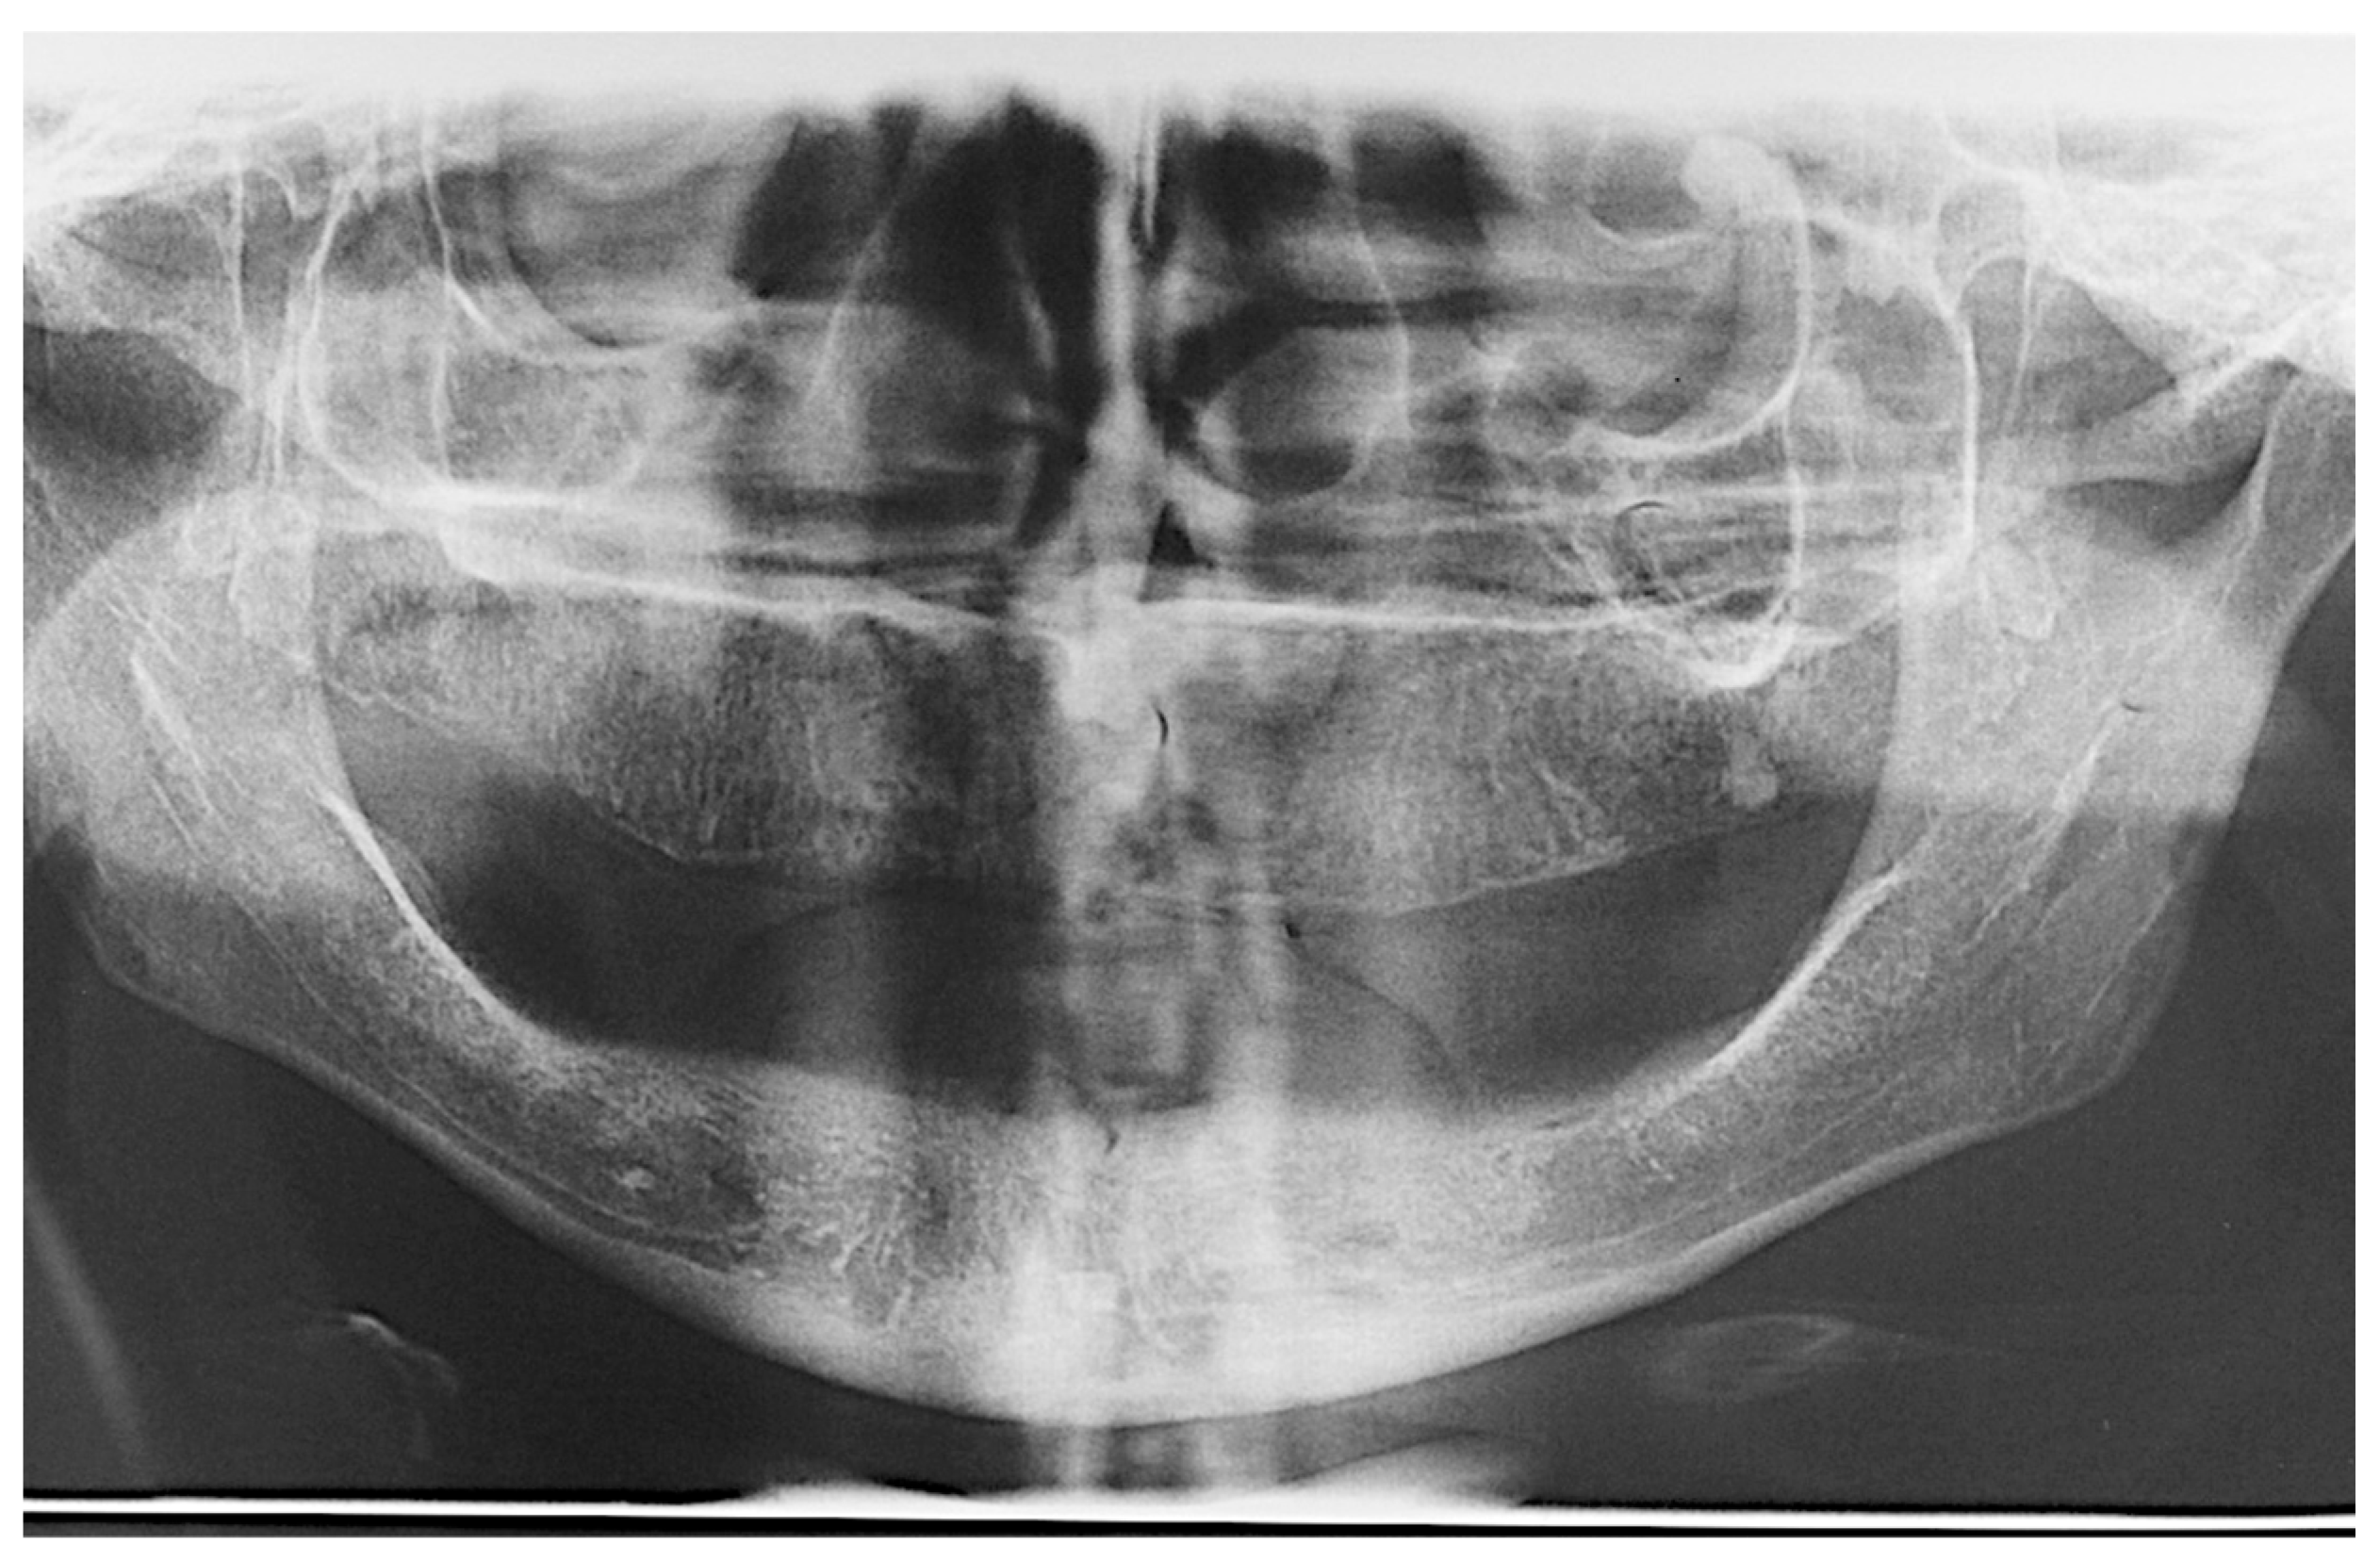

Patients were followed up for two years after implant installation, according to the following appointment schedules: time intervals of 7 days, 60 days, 6 months, 12 months, 18 months and 24 months [21]. The success criteria used in this study were, as suggested by Misch [23], no mobility, no pain during function, less than 2 mm of radiographic bone loss after initial surgery and no history of exudates. The clinical parameters of the implants were assessed during all follow-up appointments. Patients were examined using periodontal probing, CT scans, radiographs (Figure 13), intra- and extra-oral photographs and ISQ assessment.

Figure 13.

Two-year follow-up control panoramic radiograph.